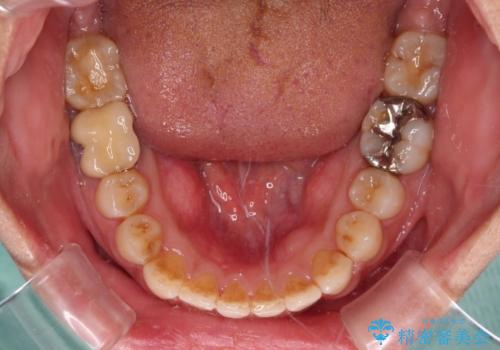

前歯のデコボコとクロスバイト インビザラインによる矯正治療

懸念されたとおり、右下のクラウン部分が全く咬み合わず、仕上げの段階で治療期間が長くなりました。